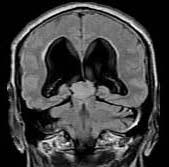

问题 15岁,男,头痛、呕吐,步态不稳,眼球震颤,性发育异常,MRI检查如图,最可能的诊断()

选项 A.松果体钙化 B.松果体瘤 C.脑膜瘤 D.生殖细胞瘤 E.畸胎瘤

答案 B